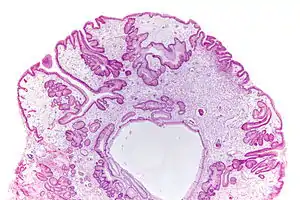

| Micrograph of a gastric juvenile polyp, as may be seen in juvenile polyposis syndrome. H&E stain | |